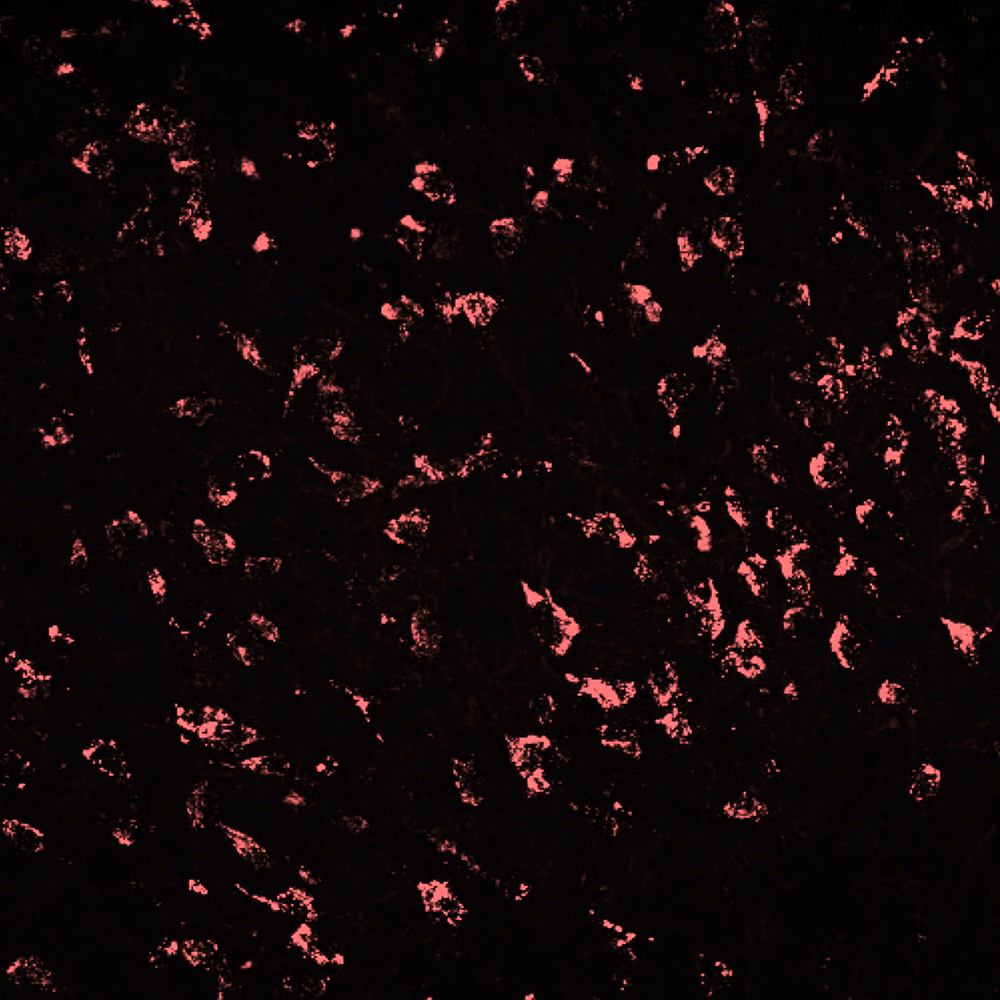

Our research shows that overfeeding in early life can contribute to central inflammation that may permanently influence hypothalamic feeding and stress circuitry; leading to an increased propensity to gain weight and stay fat, hyperactive responses to stress, infertility, and an inability to appropriately respond to inflammatory challenges.

We have a particular focus on the role of microglia in these effects and are also establishing microglia’s role in healthy brain function, including appetite and cognition.